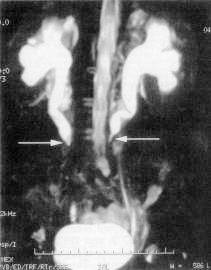

• болезнь Ормонда - фотоИнструментальные методы. На обзорной рентгенограмме почек и верхних мочевыводящих путей определяют расплывчатость контуров поясничной мышцы и очертаний почек. Экскреторная урография позволяет выявить длинные суженные участки мочеточника и его медиальное отклонение в проекции средней трети, а также гидронефронефротическую трансформацию и характерные изменения мочеточников — расширение до среднего физиологического сужения (обструкция за счёт сдавления извне) со смещением в медиальную сторону. Аналогичную картину выявляет ретроградная пиелоуретерография. Тем не менее, при РПФ медиальное отклонение возникает не всегда, в то время как у 20% людей с нормальными мочевыводящими путями также выявляют данное отклонение мочеточников. Таким образом, по данным уретеропиелограмм, триада, указывающая на наличие болезни Ормонда, включает:

• гидронефроз с расширенным извилистым верхним сегментом мочеточника;

• медиальную девиацию мочеточника;

• наружную компрессию мочеточника.

При невозможности выполнения ретроградной производят чрезкожную антеградную пиелоуретерографию. С помощью радиоинуклидного исследования оценивают функциональное состояние почек и верхних мочевыводящих путей. Ультразвуковое исследование подвздошных сосудов с цветным допплеровским картированием подтверждает расширение полости почки и мочеточника и выявляет прерывание мочеточника на уровне его перекреста с подвздошными сосудами. Определенное диагностическое значение имеет венокаваграфия. Для заболевания характерны сужение или обструкция нижней полой вены с развитием коллатералей, а также смещение её поясничного отдела кпереди. В последнее время для диагностики РПФ используют КТ и МРТ. Данные виды медицинского обследования позволяют выявить не только расширение верхних мочевыводящих путей, но и однородное объёмное образование, окружающее мочеточник, нижнюю полую вену и аорту. Учитывая, что ретроперитонеальный фиброз может возникнуть вследствие воспалительных заболеваний соседних органов, целесообразно провести обследование органов брюшной полости и малого таза.